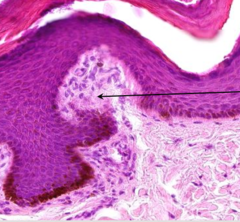

epidermal ridge

Front

what part of the epidermis is this?

Back